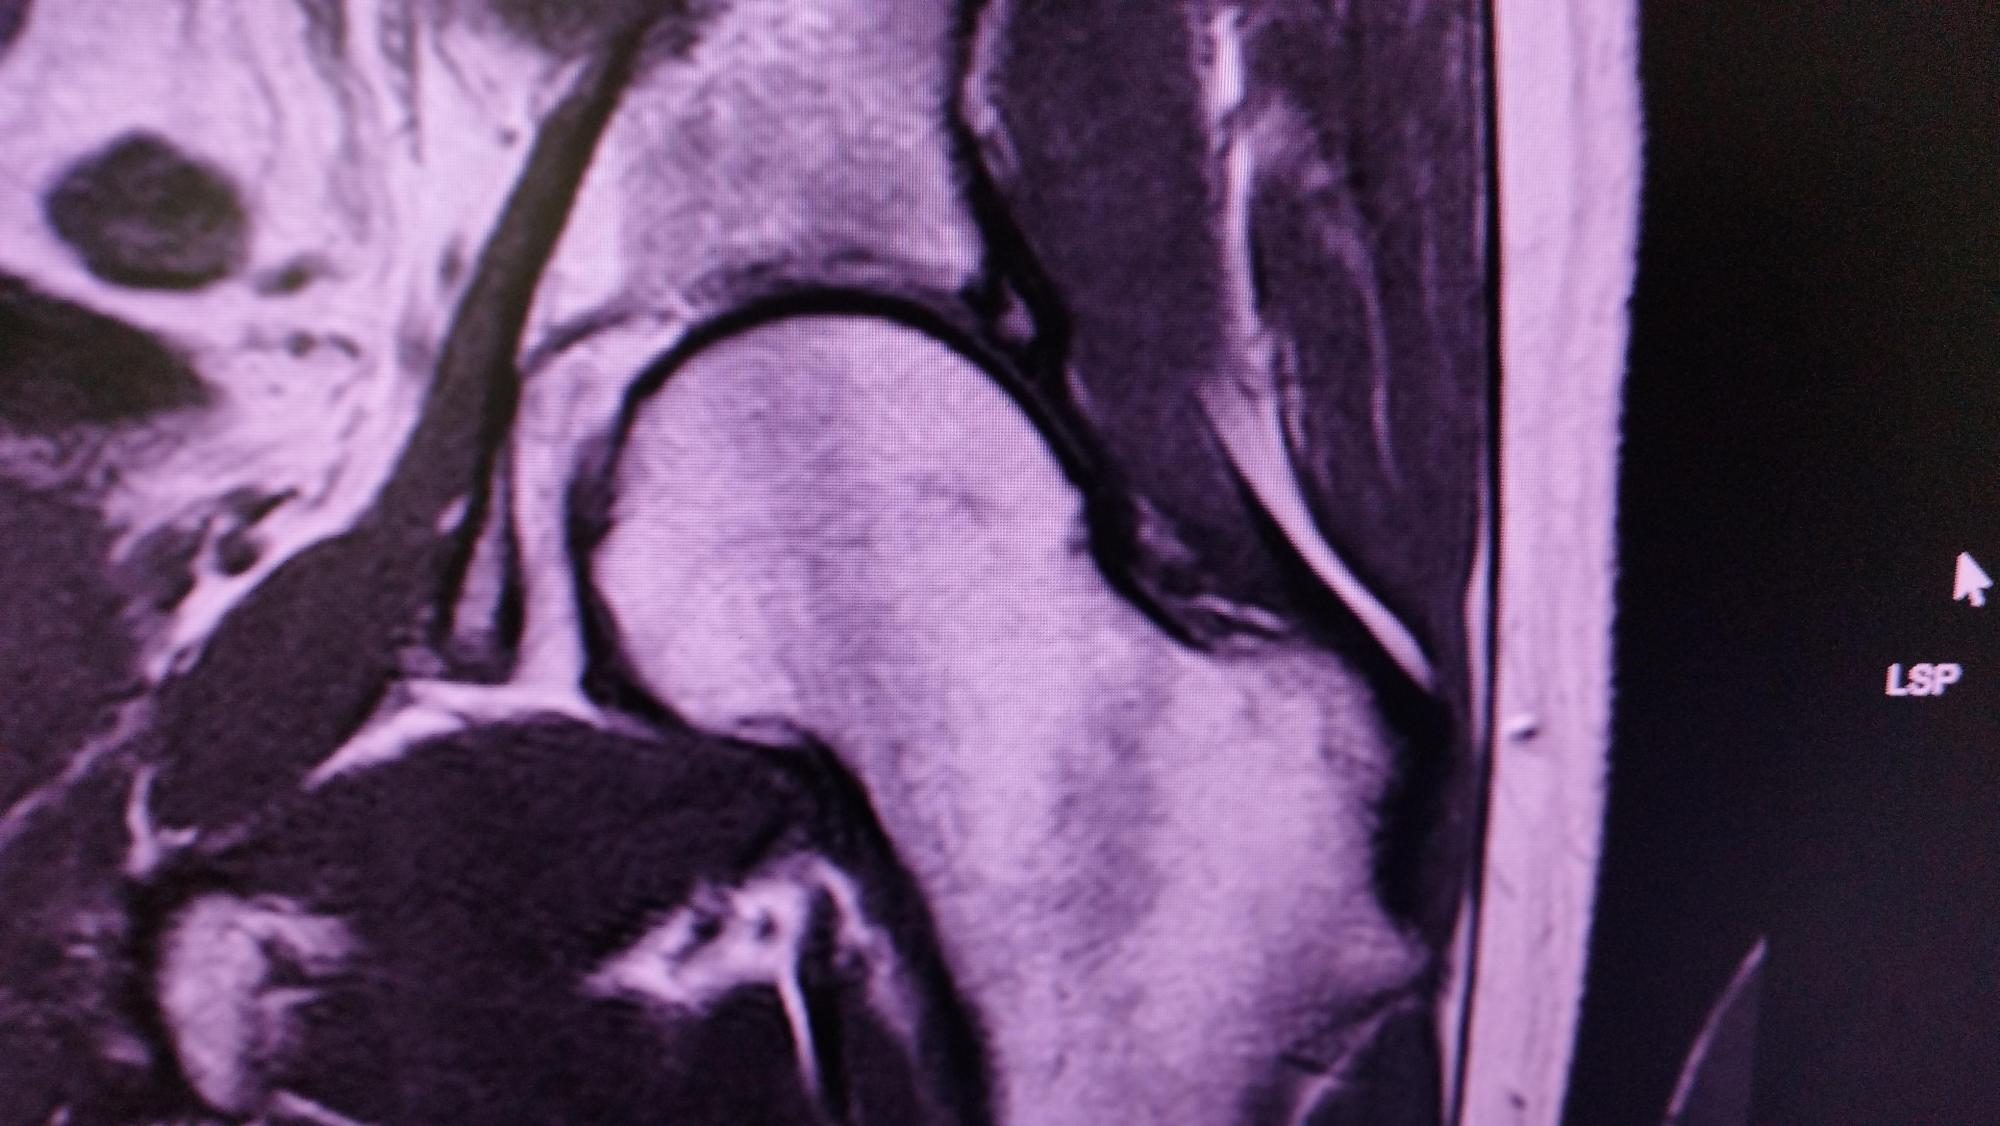

Hier die Ergebnisse des ersten MRT:

Keine Arthrose. Verdacht auf eine kleine Labrumläsion, Geringer Reizzustand am Kapselligament. Geringer Reizzustand am linken ISG. Ich war dann

erstmal etwas beruhigter.

Hier die Ergebnisse des zweiten MRT:

Beidseits Zeichen eines Pinzer CAM-Impingements. Gelenkspalt beidseitig kranial leicht verringert. Ganglion am Ansatz des Labrums ohne Nachweis

auf Rissbildung. Geringe Insertionstendiopatie.

Berichte beider MRTs und Bilder aus dem ersten MRT im Anhang

IMG_20240408_152407.jpg

IMG_20240408_152424.jpg